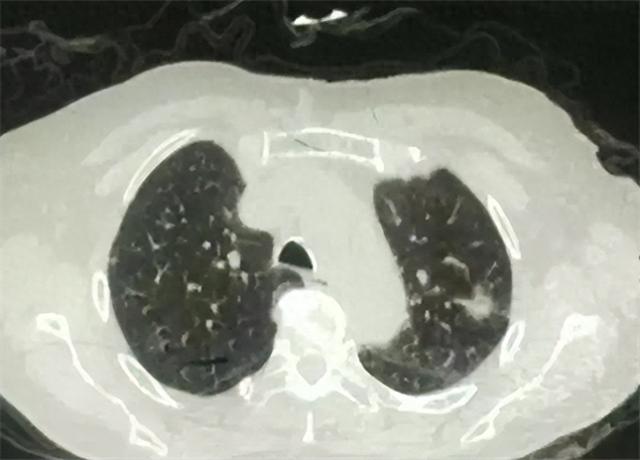

肺部CT检查作为一种先进的医疗成像技术 , 对于诊断各种肺疾病具有至关重要的作用 。 这项检查通过使用X射线和计算机处理技术 , 能够提供关于肺部以及呼吸系统其它部位的详细横截面图像 , 从而帮助医生对肺部疾病进行更精确的诊断和评估 。

肺部CT检查主要用于发现、诊断以及跟踪肺部的炎症、感染、肿瘤、血管问题以及其它肺部病变 。 它能够精确描绘肺部结构 , 包括细小气道、肺泡以及周围血管的状况 , 对于早期检测肺部微小结节、评估肺癌扩散、确识慢性阻塞性肺疾病的程度以及检查间质性肺病等具有不可替代的作用 。

1. 肺结节的大小、形态和边缘特征:

肺结节是肺部CT中常见的发现 , 其重要性在于它们可能是早期肺癌的指标 。 需要特别关注的是肺结节的大小、形态和边缘特征 。 一般而言 , 直径小于6mm的小结节 , 其恶性可能性较低 , 但这不是绝对的 。

结节的形态和边缘特征也很关键 , 不规则形状或模糊、毛糙的边缘更可能提示恶性变 。 此外 , 含钙化的结节多为良性 。 这些特征的评估对于确定后续的监测策略或是否需要进一步的活检检查具有重要意义 。

肺实变是指正常的肺组织被液体、炎细胞、血液或其他替代物质填充所致的密度增高 。 肺部实变可能是肺炎、肺栓塞或肺癌等疾病的表现 。 肺部CT上见到的实变区域需要关注其分布特点、形状及是否伴有空洞形成等 , 这些都对疾病的诊断和鉴别诊断具有重要价值 。

肺间质疾病是一组影响肺部支架结构的疾病 , 包括纤维化、炎症和肺水肿等 。 肺部CT扫描中的间质改变通常表现为网格状阴影、小叶间隔增厚或蜂窝状改变等 。 肺间质的改变是评估肺纤维化程度、分析其分布特点及确定可能的病因的重要依据 。

胸膜包括覆盖在肺表面的脏层胸膜和贴近胸壁的壁层胸膜 , 二者之间形成的薄薄的胸膜腔 。 肺部CT扫描中应重视胸膜的厚度、是否有胸膜积液以及是否有胸膜增厚或胸膜斑块等异常 。 胸膜异常可能是胸膜炎、胸膜肿瘤等疾病的表现 , 对判断疾病的性质和严重程度具有重要意义 。